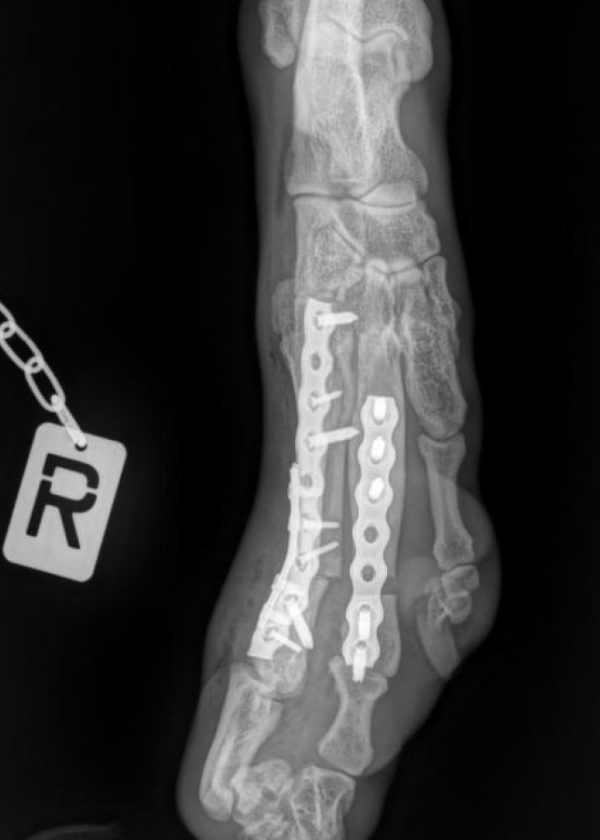

Wir machten uns also wieder auf die Reise in die Tierklinik Dresdner Heide, wo sich Dr. Pfeil schon vor ein paar Wochen ein Bild von der Behinderung gemacht hatte. Pamukelchen musste stationär aufgenommen werden, da viele Untersuchungen nötig wurden. Es wurden CT Scans gefertigt, unzählige Röntgenaufnahmen in den verschiedensten Positionen, Diagramme erstellt, Blut untersucht. Da diese Art der Behinderung noch nie vorlag, mussten viele Überlegungen angestellt werden und es stand fest, dass es eine schwerwiegende OP wird. Unsere süße Maus lies tapfer alles über sich ergehen und war ganz brav. Und endlich, nach sieben Tagen Klinikaufenthalt konnten wir Pamukel und auch Tofie, der in dieser Zeit ebenfalls dort operiert worden war, wieder zu uns holen. Die Freude bei dem Wiedersehen war bei beiden natürlich riesengroß und Pamukelchen hüpfte wie ein kleines Fohlen umher.